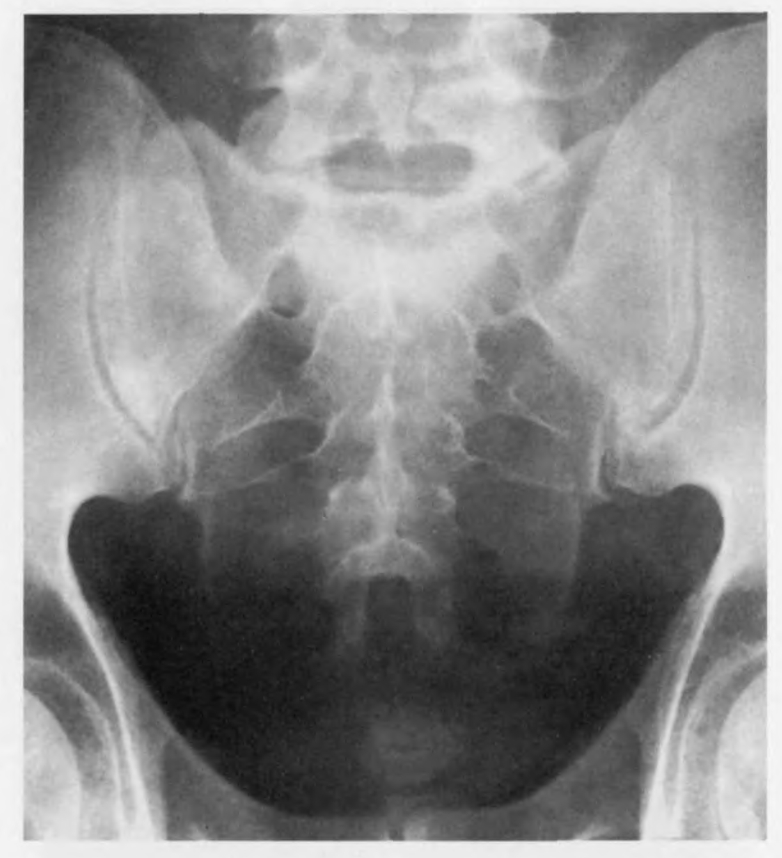

Снимок копчика